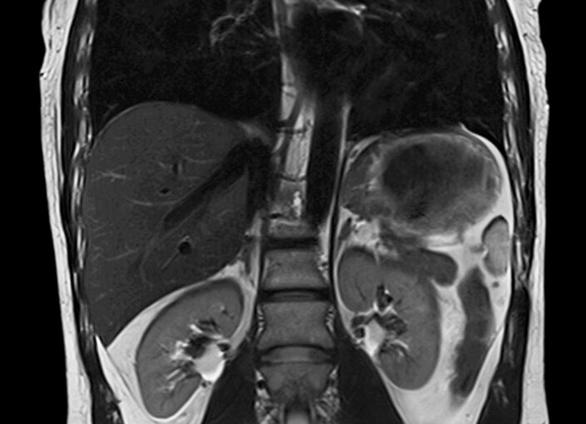

МРТ почек с надпочечниками и забрюшинным пространством помогает выявить как злокачественные, так и доброкачественные патологии. Назначается обследование и при травмах, для уточнения других диагнозов, в частности, подозрения на опухоль почки или выделительной системы. Требуется оно и при заболевании лимфатических узлов, изменениях в клетчатке и выявлении иных патологий.

Почки и надпочечники

МРТ почек позволяет диагностировать следующие заболевания:

- аномалии развития,

- абсцессы почек,

- поликистоз (кисты в почках)

- гидронефроз,

- камни в почках,

- воспалительные заболевания (пиелонефрит, гломерулонефрит, туберкулез),

- оценка опухоли (к примеру, карцинома или переходно-клеточный рак),

- оценка при ксантогранулематозном пиелонефрите,

- оценка доброкачественных опухолей (к примеру, онкоцитома и ангиомиолипома);

Однако наибольшую ценность МР-исследование представляет в дифференциальной диагностике опухолей и кистозных образований почек.

МРТ позволяет выявить новообразования менее 2 см в диаметре, обнаружить метастазы в лимфатические узлы и опухолевые тромбы в сосудах почки.

Исследование почек и надпочечников

Диагностически значимо при новообразованиях (доброкачественных и злокачественных), кистоподобных и других объемных образованиях и их дифференциальной диагностике, при врожденных особенностях развития.

Опухоли почек